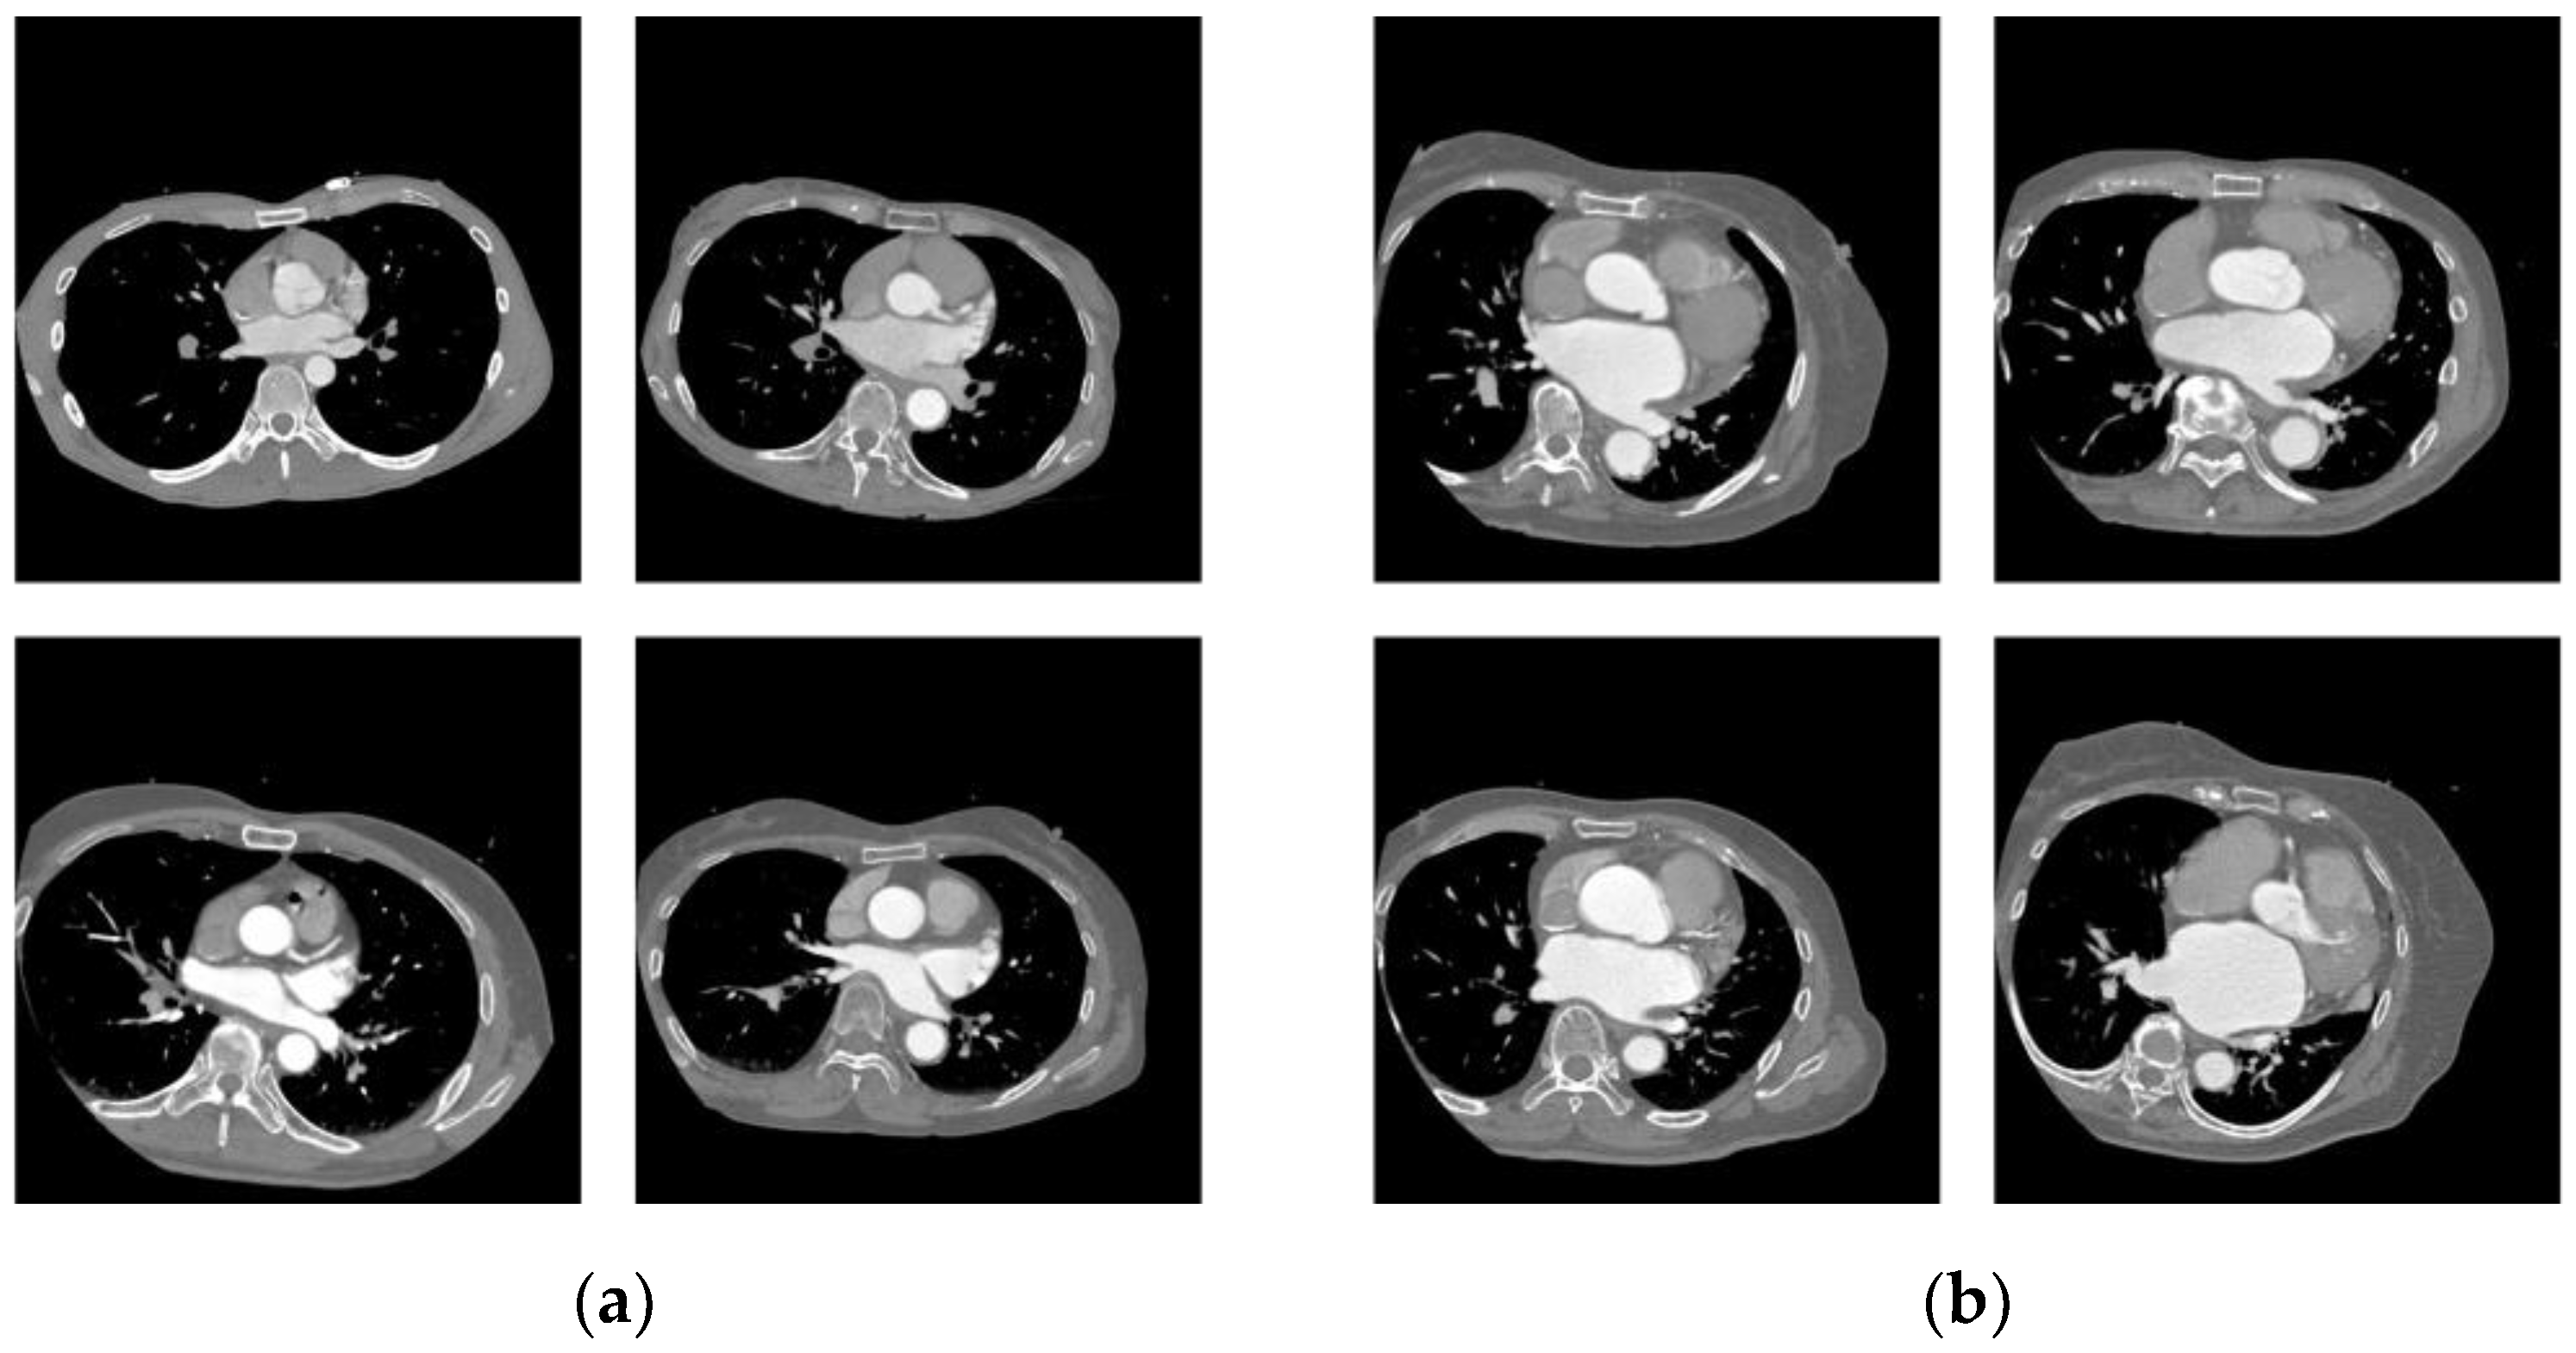

The images that were correctly classified by ResNet50 are shown in Figure 7, and those that were incorrectly classified are shown in Figure 8.

Figure 7.

Correctly classified cases. (a) PAF; (b) LSAF.

4.3. Comparison with Physician’s Results

In response to the physician’s description of the basis for judgment, enlargement of the left atrium is a feature of LSAF in many cases. In the correctly classified cases shown in Figure 7, (a) the PAF has a small, flat left atrial structure, whereas (b) the LSAF has a large, rounded left atrial structure in the front and back. The CNN model is expected to classify patients using the same criteria as physicians because the heatmap also shows that the left atrium area attracts more attention. The cases in which the CNN model and averaged results of the physicians’ responses differed are shown in Figure 13. Case (a) involved LSAF, but the left atrium was relatively small (left), and there was no loss of the pectinate muscle structure (right). The CNN model can classify these cases. However, it was misclassified, even when the typical findings of LSAF in the size of the left atrium were observed, as shown in (b). The possible reason is that by using the entire CT image as the input image, information other than the left atrial region may have led to misclassification. This problem could be improved by increasing the variation with more training data and narrowing the field of view to the left atrial region alone.